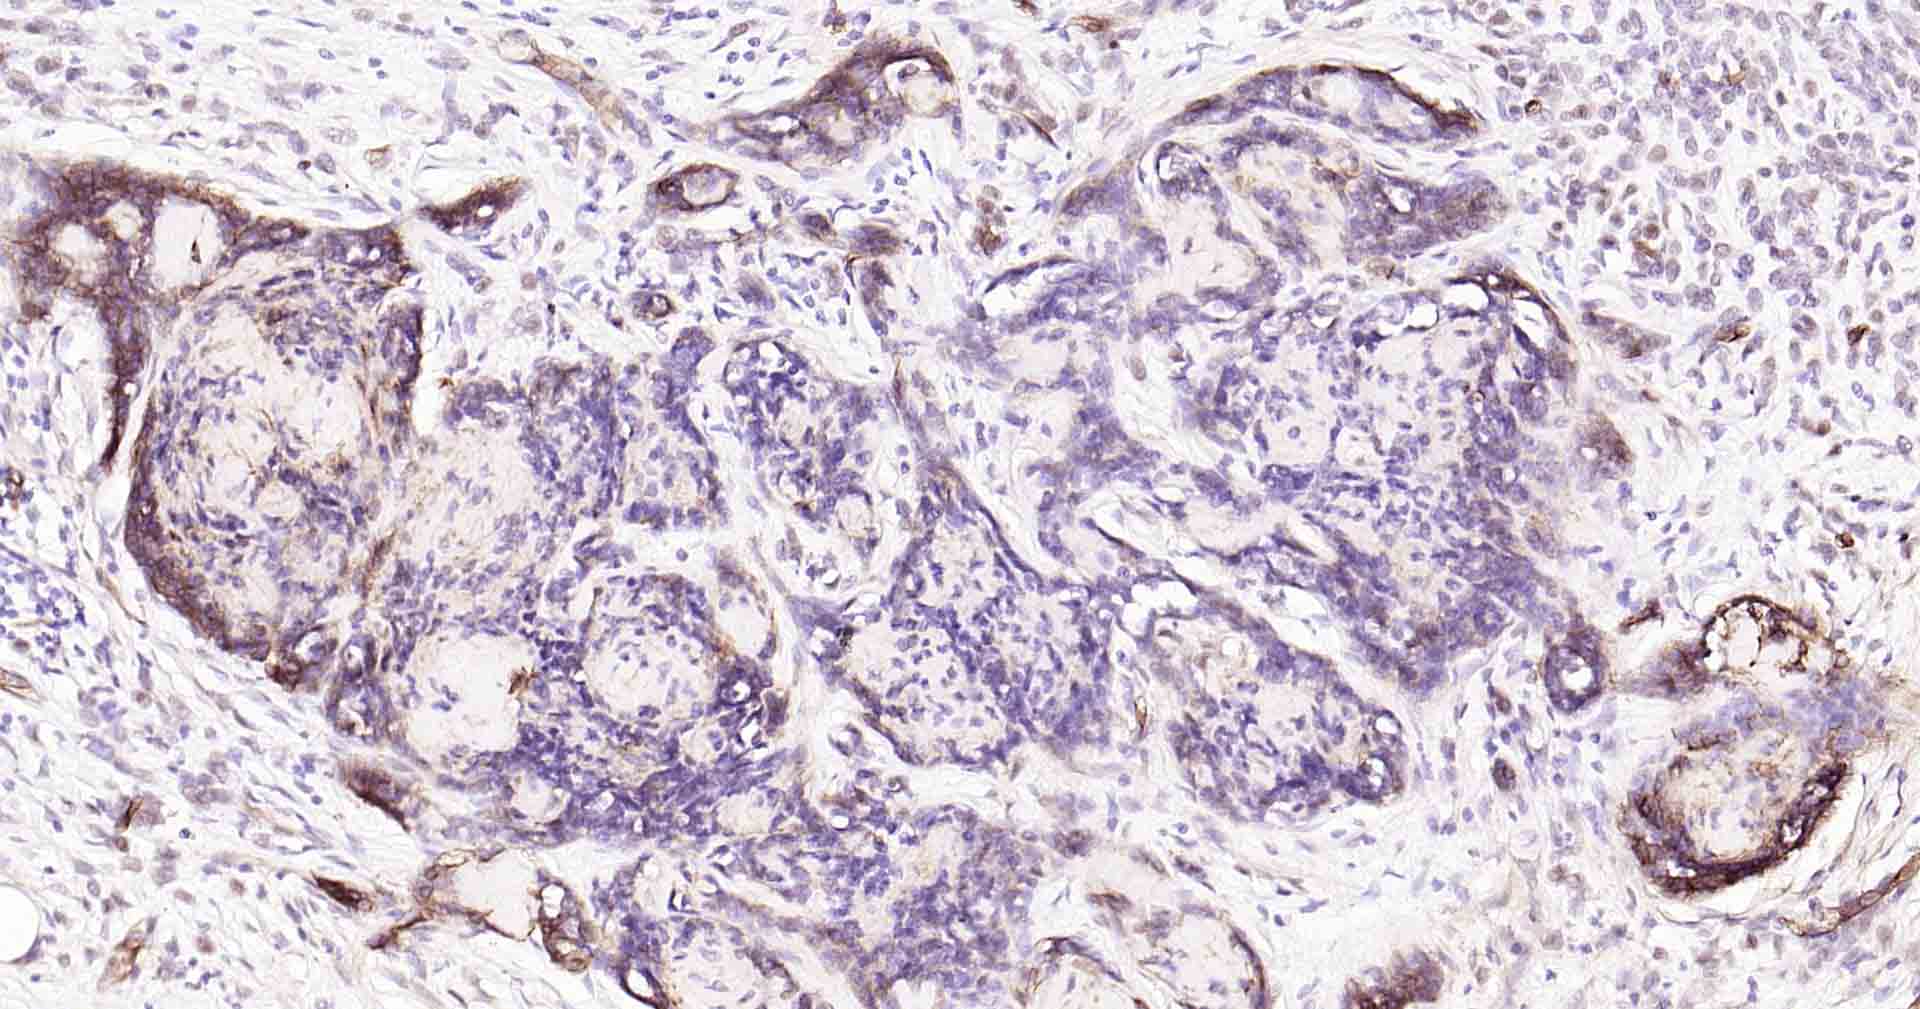

Paraformaldehyde-fixed, paraffin embedded Human Breast Cancer; Antigen retrieval by boiling in sodium citrate buffer (pH6.0) for 15 min; Antibody incubation with AQP1 Monoclonal Antibody, Unconjugated(bsm-52909R) at 1:200 overnight at 4°C, followed by conjugation to the SP Kit(Rabbit, SP-0023) and DAB (C-0010) staining.